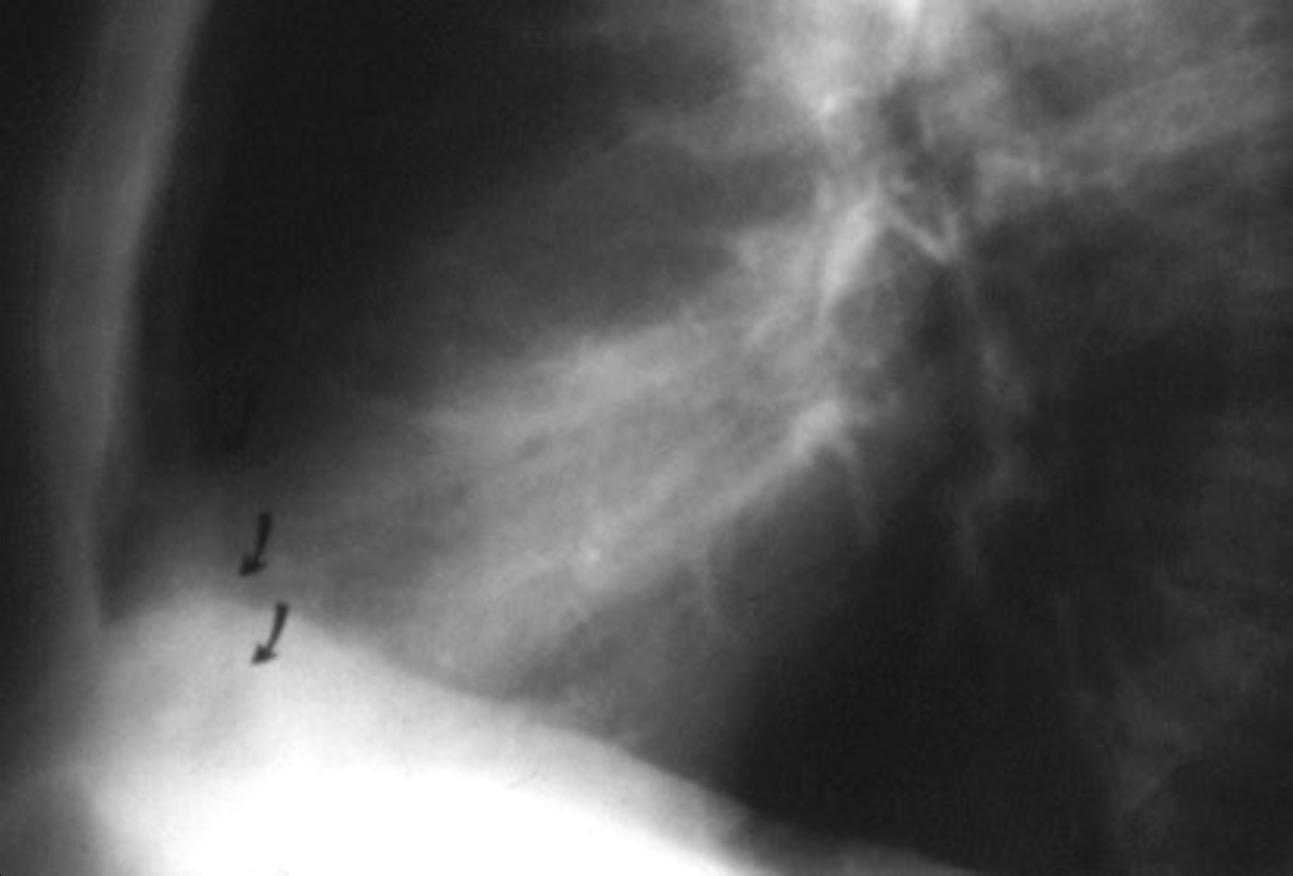

Paciente que ingresa con síntomas de colecistitis aguda. Antecedentes de trauma importante muchos años antes

Zhao L et al. Delayed traumatic diaphragmatic rupture: diagnosis and surgical treatment. © Journal of Thoracic Disease.

J Thorac Dis 2021

Asas

Líquido pericolecistítico

V. biliar con cálculos

Diafragma